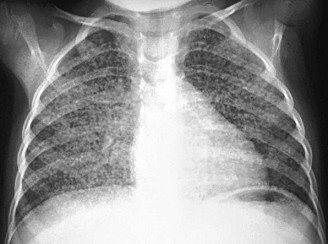

TB

lung with tubercles, X-ray photo

TB lung with tubercles, X-ray photo [1]